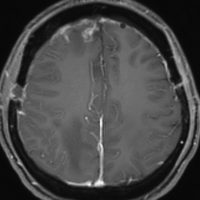

H字状皮膚切開で広範囲両側前頭登頂開頭をして,穹窿部と傍矢状洞部髄膜腫をほとんど摘出してしまいました。上矢状洞は開存していたので残してあります。